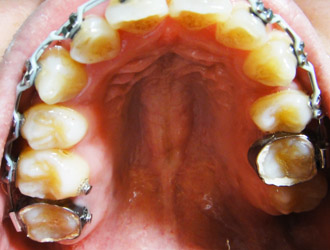

上個月開始將左上的凹牙拉出來後,終於可以上下排矯正器了,

果真如醫生所預期的,大概半年才能裝下排。

(本篇有亂齒照,慎入!)

從今年2月初矯正至今滿4個月囉!

朋友問矯正過程會不會痛? 其實最痛苦的是第一個月,之後則不太會去注意它,或許是身體很容易習慣?

最不舒服的就是塞藍色橡皮筋和剛調整完線第一天吃東西的時候,之後幾個月就沒感覺了。